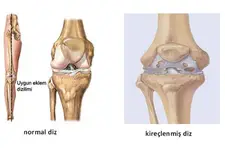

Diz kıkırdak aşınması, diz eklemindeki kıkırdak dokusunun zamanla bozulması ile ortaya çıkan bir durumdur. Yaş, aşırı kullanım, yaralanmalar ve obezite gibi faktörler bu durumu tetikler. Belirtiler arasında ağrı, sertlik ve hareket kısıtlılığı yer alır. Tedavi yöntemleri ise ilaç, fiziksel terapi ve cerrahi seçenekleri içermektedir. Bu yazıda, diz kıkırdak aşınmasının belirtileri, nedenleri ve tedavi yöntemleri detaylı bir şekilde ele alınmaktadır.

Diz Kıkırdak Aşınması Belirtileri ve Tedavisi Diz kıkırdak aşınması, diz ekleminde bulunan kıkırdak dokusunun zamanla bozulması ve incelmesi durumudur. Bu durum, genellikle yaşlanma, aşırı kullanım, yaralanmalar ve obezite gibi faktörlerden kaynaklanmaktadır. Kıkırdak, eklemler arasında amortisör görevi görerek, kemiklerin birbirine sürtünmesini önler. Kıkırdak aşınması, dizdeki ağrı, sertlik, şişlik ve hareket kısıtlılığı gibi belirtilerle kendini gösterir. Bu makalede, diz kıkırdak aşınmasının belirtileri, nedenleri ve tedavi yöntemleri üzerinde durulacaktır. 1. Diz Kıkırdak Aşınmasının Belirtileri Diz kıkırdak aşınmasının belirtileri, hastalığın ilerlemesine bağlı olarak değişiklik gösterebilir. Genel olarak görülen belirtiler şunlardır:

4. Tedavi Yöntemleri Diz kıkırdak aşınması tedavisi, hastanın durumuna ve aşınmanın derecesine bağlı olarak değişmektedir. Tedavi yöntemleri şunları içermektedir: